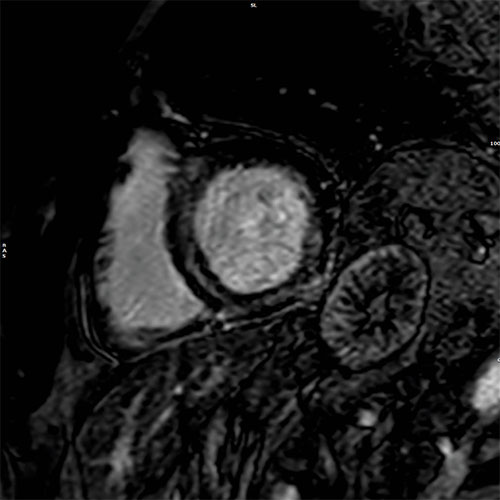

Cardiac MR images of a patient with non-ischemic cardiomyopathy showing delayed enhancement and severe mitral regurgitation.

PSIR – short axis view